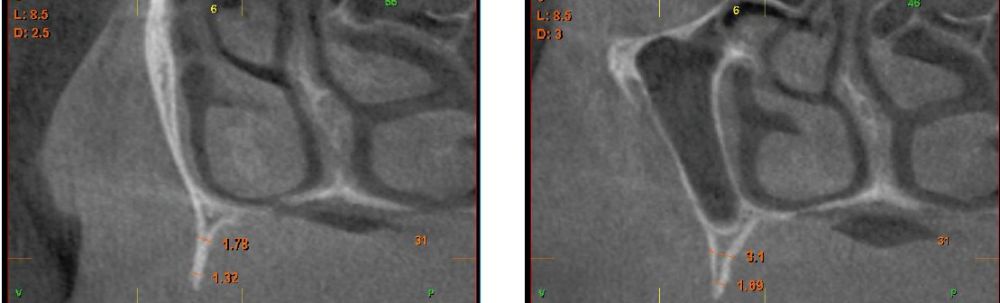

Fueron reclutados pacientes de forma retrospectiva con atrofia ósea horizontal severa (con anchura residual de cresta menor o igual a 3 mm), donde se colocasen injertos en bloque para regeneración ósea y posteriormente se insertarán implantes, con un tiempo de seguimiento tras la carga mayor o igual a 10 años. Antes de la colocación de los implantes, todos los pacientes fueron sometidos a una evaluación integral que incluyó modelos diagnósticos, un examen clínico intraoral detallado y un estudio tomográfico mediante Cone beam (TAC dental). Las imágenes obtenidas fueron analizadas con un software especializado (BTI-Scan III) para garantizar una planificación tridimensional precisa. Posteriormente, se llevó a cabo un encerado diagnóstico que sirvió como base para la creación de una guía quirúrgica, optimizando la ejecución de la rehabilitación planificada. La posición final de los dientes obtenida del encerado será la que guíe el proceso de regeneración para lograr el volumen óseo necesario para colocar los implantes en la posición necesaria. Antes de la inserción de los implantes se utilizó una pre-medicación antibiótica consistente en amoxicilina 2gr vía oral una hora antes de la intervención y paracetamol 1 gramo vía oral (como analgésico). Posteriormente los pacientes prosiguieron con un tratamiento de amoxicilina 500-750 mg vía oral cada 8 horas (según peso) durante 5 días. Todos los injertos se obtuvieron de rama mandibular y fueron divididos en cortical y esponjosa, según la técnica de Khoury18. Se conservaron en PRGF-Endoret hasta el momento de su uso y el hueso particulado obtenido de la parte medular del injerto se colocó embebido en PRGF-Endoret fracción 2 sin activar. Una vez posicionados los injertos fueron fijados mediante material de ostesíntesis (KTOÒ– Biotechnology institute) y toda la zona intervenida se cubre con membranas de fibrina autóloga (PRGF-Endoret fracción 1 activada y retraída) antes de la sutura con monofilamento de 5/0 para lograr cierre primario. Los injertos maduran 4-5 meses y posteriormente se realiza un nuevo Cone beam para conocer la anchura lograda y planificar la inserción de los implantes. La inserción de los implantes fue realizada por un mismo cirujano, mediante la técnica de fresado biológico, a bajas revoluciones, sin irrigación26-28. Una vez transcurridos cuatro meses desde la inserción de los implantes, se lleva a cabo la carga de los mismos mediante una prótesis provisional de carga progresiva elaborada en resina, con estructura metálica de barras preformadas y atornillada a transepiteliales. Estas prótesis provisionales se mantienen de 3 a 6 meses, en función de la adaptación y requerimientos de cada paciente. Una vez transcurrido este tiempo se realizan las prótesis definitivas. Tras la colocación de las prótesis definitivas los pacientes entran en un programa de seguimiento al que acuden cada 6 meses. En estas visitas se realizan radiografías panorámicas de control y periapiacales en la zona de inserción de los implantes. Las radiografías periapicales se llevan a cabo con posicionador, para generar imágenes reproducibles y los pacientes son colocados para la radiografía panorámica con posicionador fijo en glabela y mentón, mordedor para zona interincisal con eje de línea media, plano bipupilar y frackfort (marca láser) y con los pies sobre marcas trazadas en el suelo, con el propósito de que sean altamente reproducibles los resultados. Sobre estas radiografías se llevan a cabo las mediciones necesarias para comprobar la estabilidad y pérdida ósea crestal de los implantes. Una vez obtenida la radiografía en formato digital es calibrada mediante un software específico (ImageJ) a través de una longitud conocida como es el implante dental. Una vez introducimos la medida de calibración, el programa informático realiza un cálculo basado en esta medida para eliminar la magnificación, pudiendo realizar mediciones lineales exentas de este error. En la visita final de seguimiento (10 años) se lleva a cabo un nuevo cone-beam para estimar la anchura ósea final tras el período de carga de los implantes y valorar la potencial reabsorción del volumen óseo logrado con la técnica regenerativa del injerto en bloque. El paciente fue la unidad de medida para el análisis de la edad, sexo y la historia médica. La variable principal estudiada ha sido el mantenimiento del volumen óseo logrado con la técnica regenerativa tras 10 años de carga. Como variables secundarias se han estudiado la supervivencia de los implantes y la pérdida ósea mesial y distal. La supervivencia de los implantes se calculó mediante el método de Kaplan-Meier. Los datos fueron analizados con SPSS v15.0 para windows (SPSS Inc., Chicago, IL, USA). Fue realizado un test de shapiro-Wilk sobre los datos obtenidos para constatar la distribución normal de la muestra.

Una vez regenerado el lecho óseo con los injertos en bloque, se obtiene una media de anchura de 6,77 mm (+/- 0,91), lo que supone un incremento medio de 5,35 mm para cada caso. En la figura 2 se muestra la anchura inicial y final para cada zona donde posteriormente se insertarán los implantes.